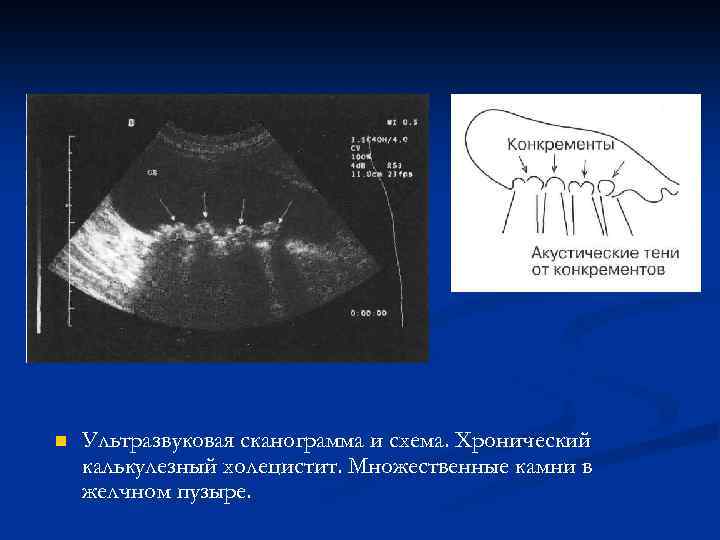

n Ультразвуковая сканограмма и схема. Хронический калькулезный холецистит. Множественные камни в желчном пузыре.

n Ультразвуковая сканограмма и схема. Хронический калькулезный холецистит. Множественные камни в желчном пузыре.